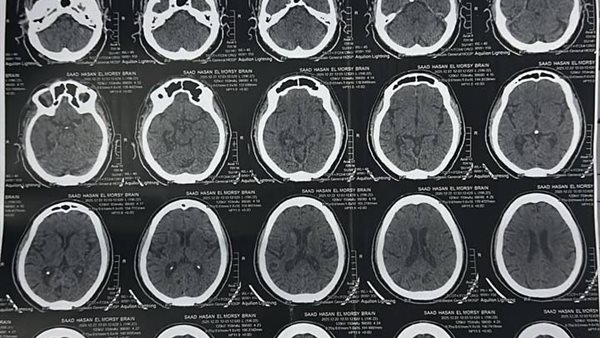

نجحت وحدة إذابة الجلطات بمستشفى السنبلاوين العام بالدقهلية، في إنقاذ حالتين حرِجتين، الأولى لمريضة تبلغ من العمر 65 عامًا وتعاني من ارتفاع ضغط الدم، كانت قد حضرت إلى قسم الاستقبال وهي تعاني من ضعف في الجانب الأيمن من الجسم والوجه.

وبعد إجراء الفحوصات والأشعة اللازمة، تم حجزها وإعطاؤها حقن إذابة الجلطات، وأسفر ذلك عن تحسن ملحوظ في درجة الوعي وخروجها بعد استقرار حالتها.

وأوضح المستشفى في بيان له، أن الحالة الثانية كانت لمريض يبلغ من العمر 70 عامًا ويعاني من مرض السكري، حضر وهو يعاني من ضعف في الجانب الأيمن وثقل في الكلام.

وبعد إجراء الفحوصات اللازمة وإعطائه حقن إذابة الجلطات، ظهر تحسن سريع في الطرفين العلويين، وخرج المريض بحالة مستقرة.